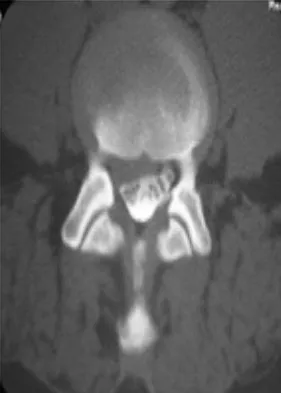

A 46-year-old woman who was involved in a motor vehicle accident reports a 4-month history of right-sided lower back pain and pain radiating into the right thigh. The patient underwent an extensive 3-month course of physical therapy and now is dependent on narcotic medication for pain control. Epidural injection therapy has failed to improve her symptoms. Examination is significant for weakness of hip flexion in the seated position and for decreased sensation to light touch in the medial anterior thigh region. Straight leg raise is negative, but the femoral stretch test reproduces anterior thigh pain. A CT myelogram image, at L3-L4, is shown in Figure 3. What is the most appropriate management at this time?